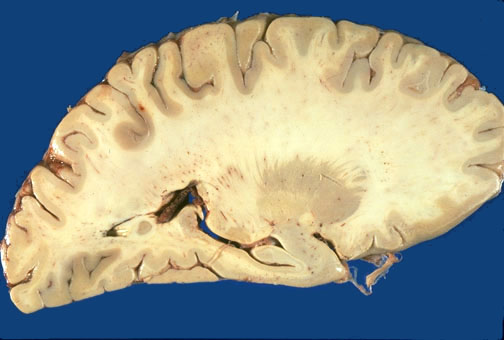

Identify the following regions of the brain on sagittal section through the hippocampus by clicking in the image below:

Putamen - Globus Pallidus - Anterior Commisure - Lateral Geniculate Nucleus - Hippocampus - Amygdala - Choroid Plexus of Lateral Ventricle - Pulvinar - Corona Radiata - Striate Area - Postcentral Gyrus